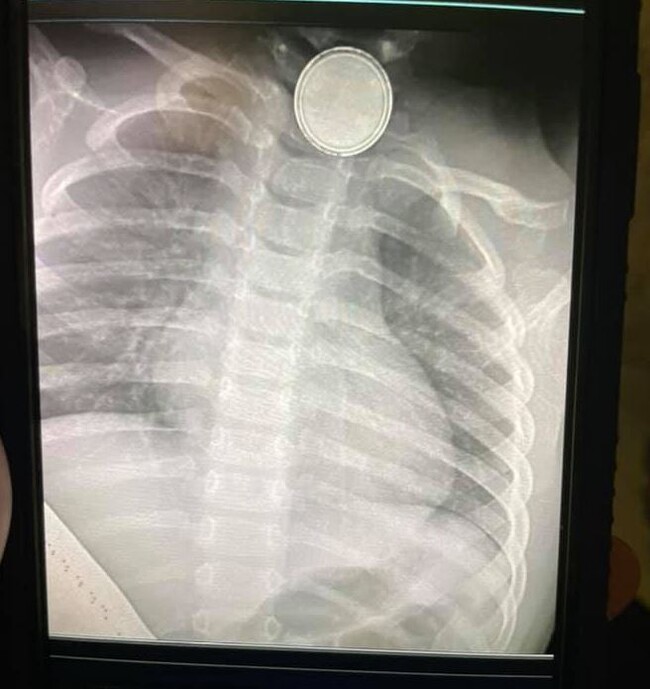

La radiografía que los médicos le hicieron a Reese en urgencias mostraba claramente la pila de botón alojada en el esófago, por lo que rápidamente decidieron intervenirla para extraérsela. Los médicos informaron a los padres de que este tipo de baterías podían causar graves secuelas, no solo porque al quedar atascadas taponan el esófago dificultando la respiración, sino porque liberan material tóxico y corrosivo que ocasiona quemaduras en los tejidos provocando lesiones devastadoras.